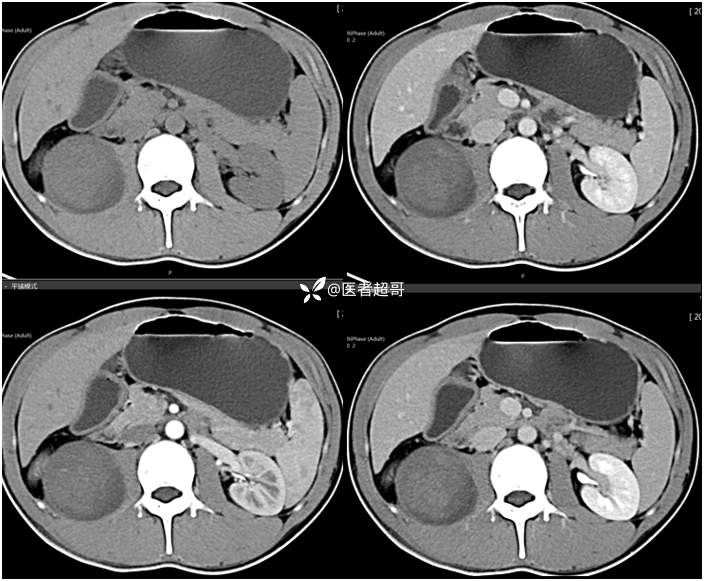

【影诊笔记754】腰痛就诊,腹膜后实性占位,请诊断分析!

主 诉:腰痛2月。

现病史:患者2月前无明显诱因出现腰背部疼痛,夜间为著。患者无头痛、头晕,无恶心、呕吐,无胸闷、憋气,无腹痛、腹胀。无尿频、尿急、尿痛等现象。患者在院外未作特殊治疗。为求进一步诊疗,来我院肾内科门诊就诊。门诊行双肾、输尿管、膀胱(前列腺)彩超提示:腹膜后实性占位。患者遂来我科就诊。我科以“腰痛”收治入院,患者自发病以来,神志清,精神可,饮食可,睡眠差。小便如上述,大便未见明显异常。体重无明显增减。